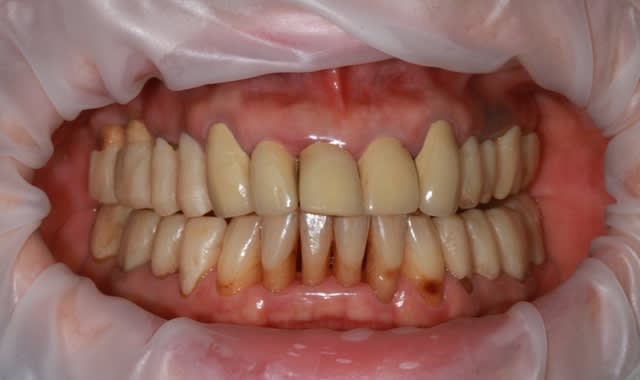

dépose des ceramo métal antérieur, ouf le précédent n'a pas mis d'IC, j'ai plus de marge de manœuvre.

Prochaine étape réalisation d'un provisoire résine "complet" pour le max.sup., mais il me faut paralléliser tous les moignons.

j'en suis à la 4eme séance détartrage surface...et ça commence à être propre et sain.

ça commence à sentir bon, dans un premier temps, les provisoires sont en place sans collage (ça marche aussi sur les dents naturelles,pas que sur les implants) pour valider la partie mécanique et permettre aux différents moignons de se positionner bien parallèle, dommage qu'il n'existe pas de "guides" pour ça...

prochaine étape collage des provisoires haut et bas, et mise en attente 1 à 2 mois.

et petit travail sur les antérieurs mandibulaires